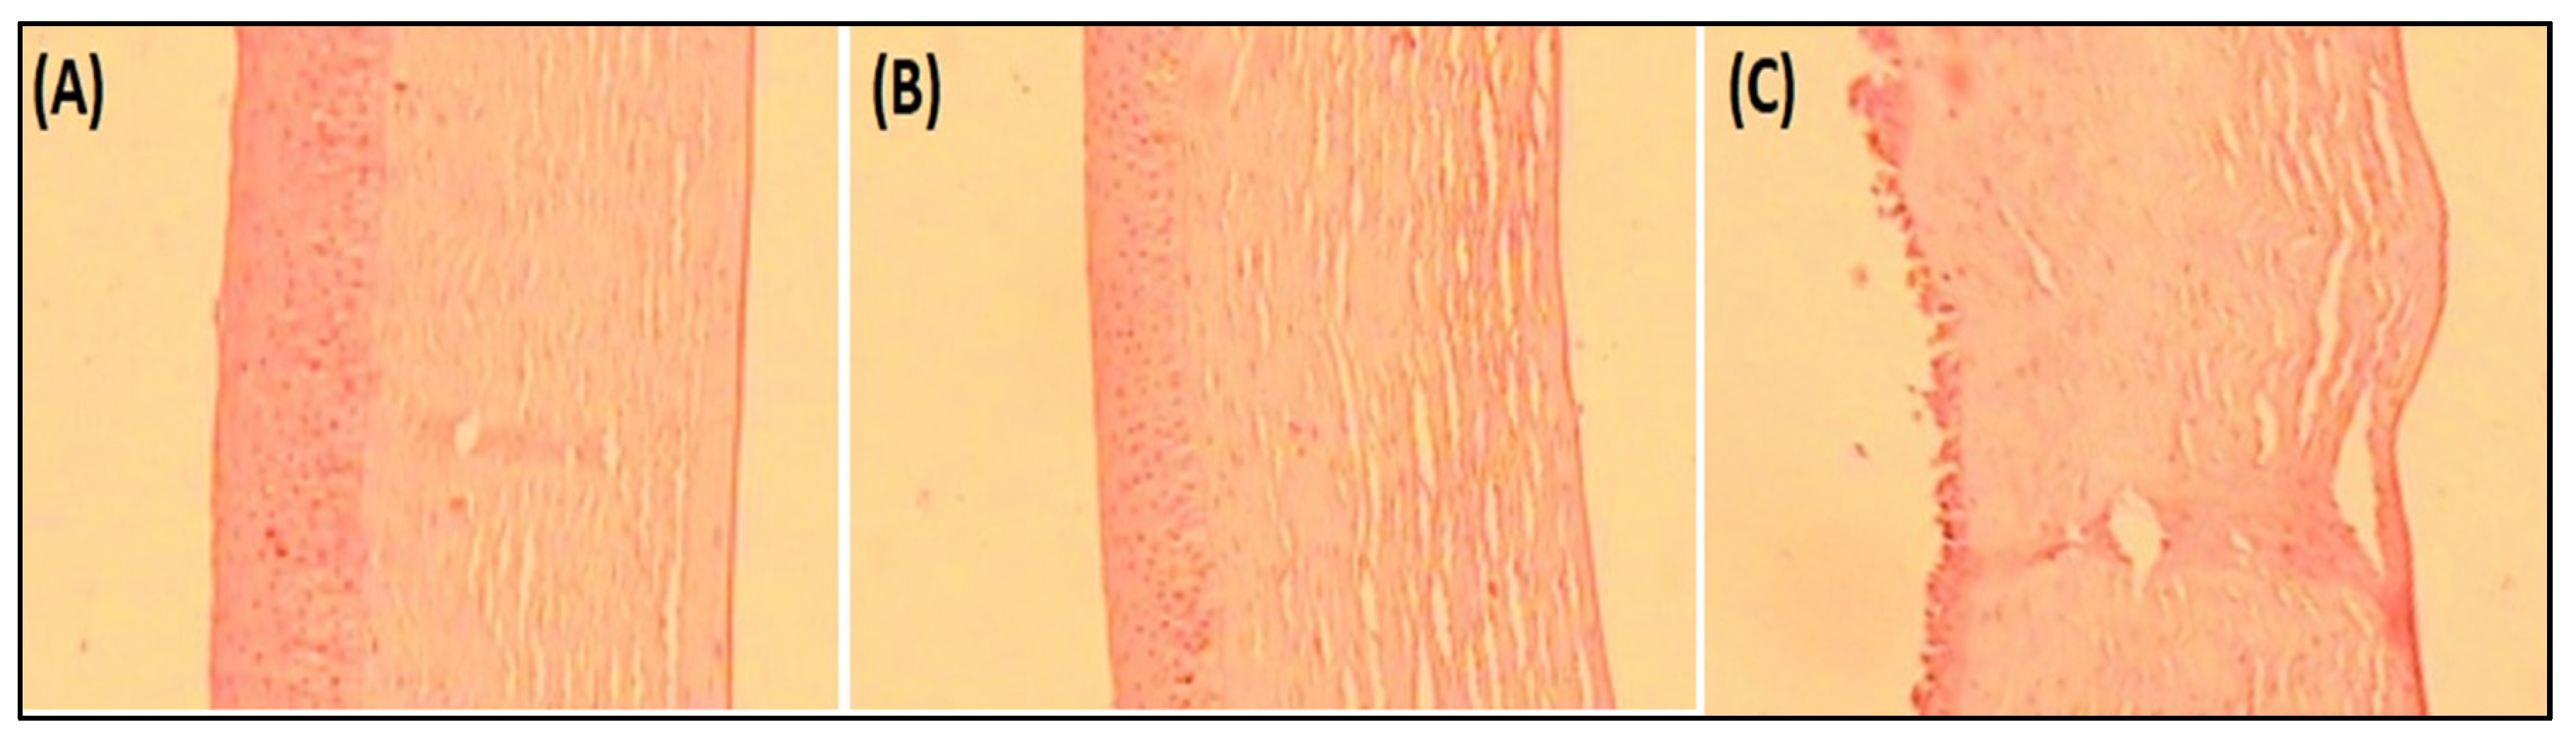

4.8.6. Histopathological Examination

4.8.7. Corneal Hydration